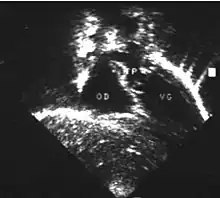

- L'échocardiographie qui est de plus en plus l'examen pratiqué en première intention. Cet examen permet d'affirmer le diagnostic en montrant les anomalies anatomiques, d'apprécier le caractère plus ou moins fonctionnel des shunts cardiaques fœtaux, de rechercher d'autres anomalies associées et dans une certaine mesure d'apprécier le retentissement de la malformation.

- Les coupes échographiques les plus utiles à cette fin sont :

- la coupe parasternale gauche grand axe : elle montre que le vaisseau issu du ventricule gauche (le plus postérieur) se dirige anormalement vers l'arrière et se bifurque précocement. C'est donc le tronc pulmonaire et non l'aorte comme normalement ;

- les coupes sous costales qui montrent bien le trajet parallèle des gros vaisseaux et leur inversion.

- Cet examen permettra d'éliminer en particulier un retour veineux pulmonaire anormal total bloqué qui aurait pu rendre compte de l’hypervascularisation pulmonaire sur la radiographie des poumons.